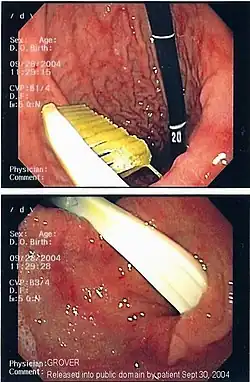

Эндоскопическое изображение инородного тела (зубной щётки) в желудке